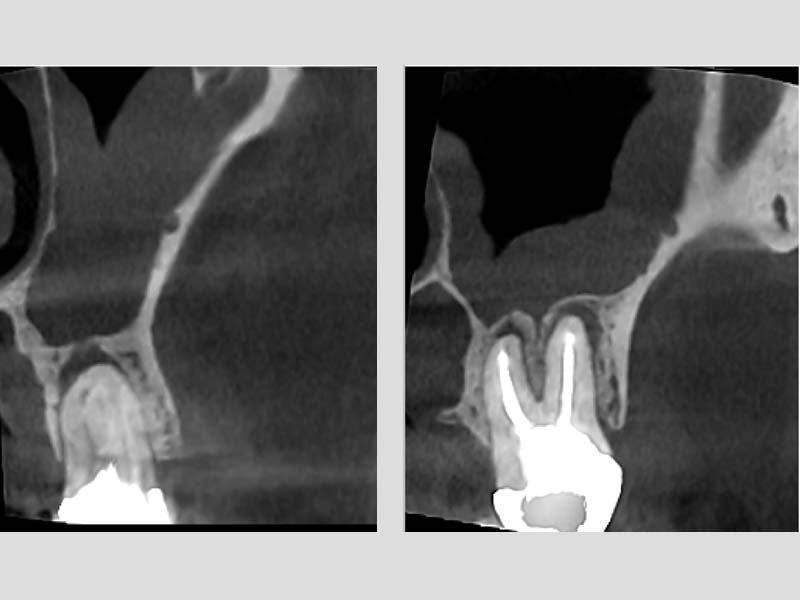

圖例為案例分享:

粉:感染增生的鼻竇黏膜

綠:原本的鼻竇範圍

紫:牙齒跟監感染,進入鼻竇

術前的電腦斷層

術後的電腦斷層,比竇黏膜已完全復原

術前 / 術後